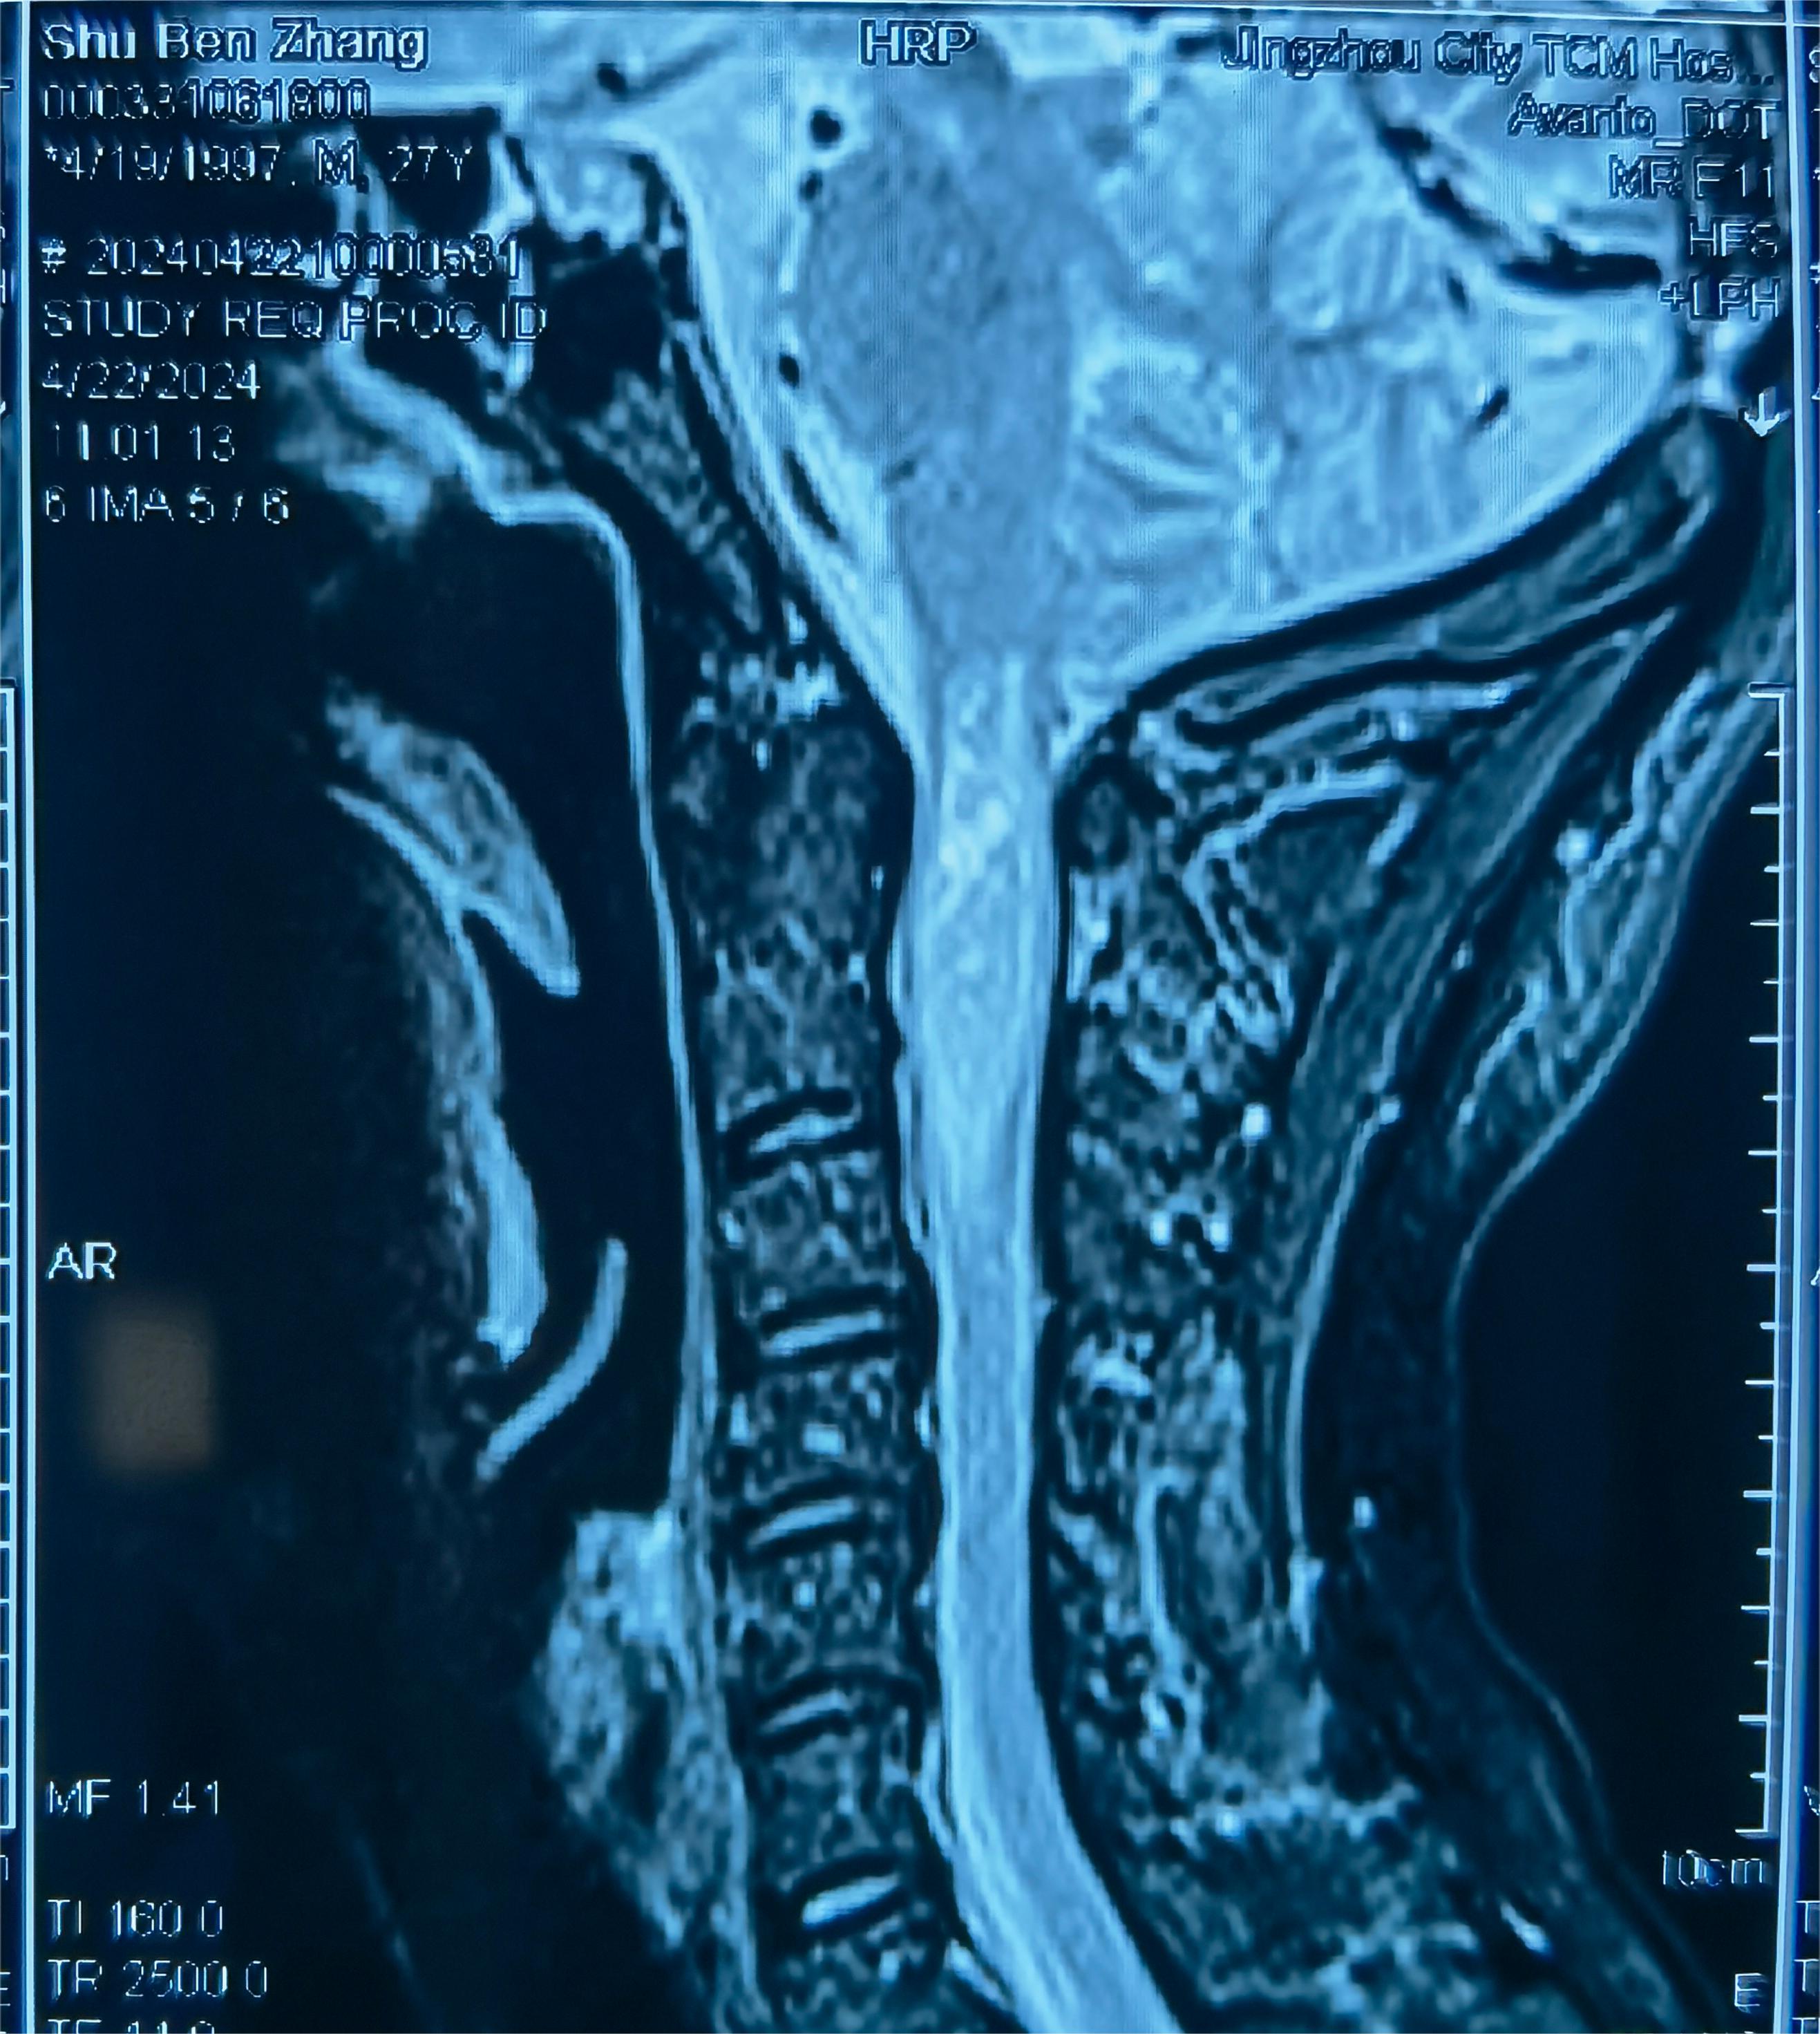

入院查头颈部MR提示C1到C2髓内占位,脊髓肿胀明显

术后MR提示肿瘤近全切除